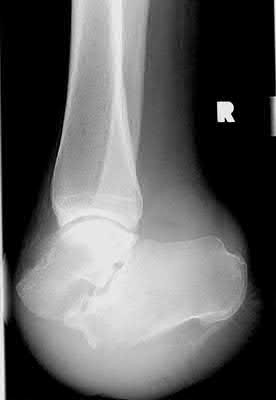

Figure A is an AP pelvic radiograph demonstrating a nonunion of a femoral neck fracture after suboptimal fixation with 3 cannulated screws in a triangle configuration.

A total hip arthroplasty (THA) after nonunion of a femoral neck fracture would provide the best long term outcomes in a 76-year-old male who is a community ambulator.

After nonunion of a femoral neck fracture, hemiarthroplasty and THA are good salvage option for the physiologically older patients. When deciding between these two options, THA is better for active and cognitively intact patients. THA is also indicated in patients with radiographic evidence of degenerative disease about the acetabulum. Hemiarthroplasty is advocated for patients who are older and less active.

Yang et al. retrospectively investigated the risk factors for nonunion in patients treated with cannulated screws. They reviewed 202 patients who had femoral neck fractures and were treated with internal fixation with cannulated screws. They identified that triangle configuration, displaced fracture, borderline or unacceptable reduction, and increased screw shaft subchondral purchase over the femoral neck were all risk factors for nonunion after internal fixation.

Inverted triangle configuration was found to increase rate of union.

Archibeck et al. retrospectively reviewed the outcomes of 102 THAs after failed internal fixation for a hip fracture (including both femoral neck and intertrochanteric). They concluded that the conversion of failed hip internal fixation has elevated risks compared to a primary THA, however, it may still be successful. The biggest concern for these patients postoperatively are periprosthetic fracture and dislocation.